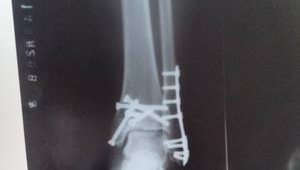

脚踝放了钢板还能踢足球吗?这些因素需考量

随着时间的推移,当骨折部位逐渐愈合,通过影像学检查确认骨折线模糊或消失后,患者可以在医生的指导下逐渐增加活动量。即使骨折已经基本愈合,脚踝放了钢板后仍存在一些潜在的风险因素。钢板作为一种异物植入体内,可能会对脚踝的灵活性和稳定性产生一定影响。在踢足球这种需要频繁变向、急停、跳跃的运动中,脚踝所承受的压力和冲击力较大,这可能会增加再次受伤的几率。